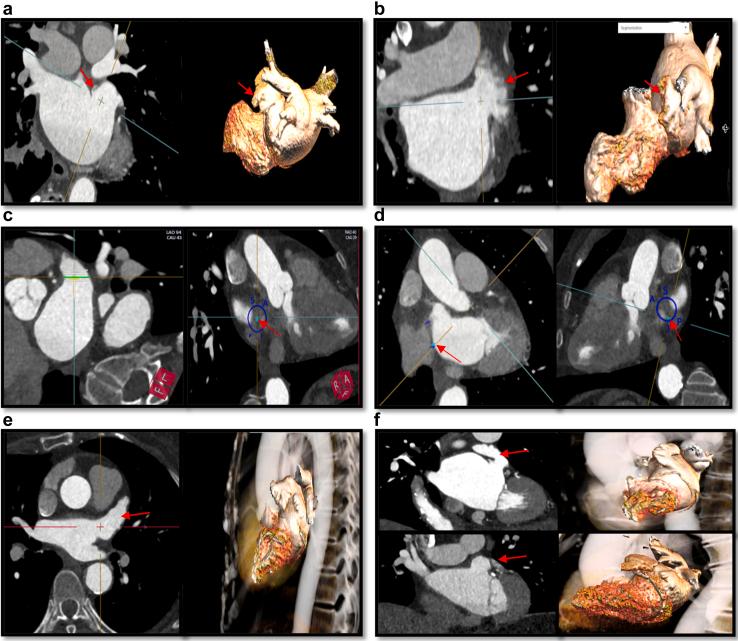

•心脏计算机断层扫描(CCT)可作为左心耳封堵术前规划的有用辅助工具。

•CCT规划包括评估排除标准、确定器械尺寸、选择鞘管、预判复杂解剖结构以及经间隔穿刺规划。

•术中三维心内超声心动图(3D-ICE)越来越多地被用于替代经食管超声心动图。在这种情况下,术前CCT有助于弥补3D-ICE分辨率降低的不足。